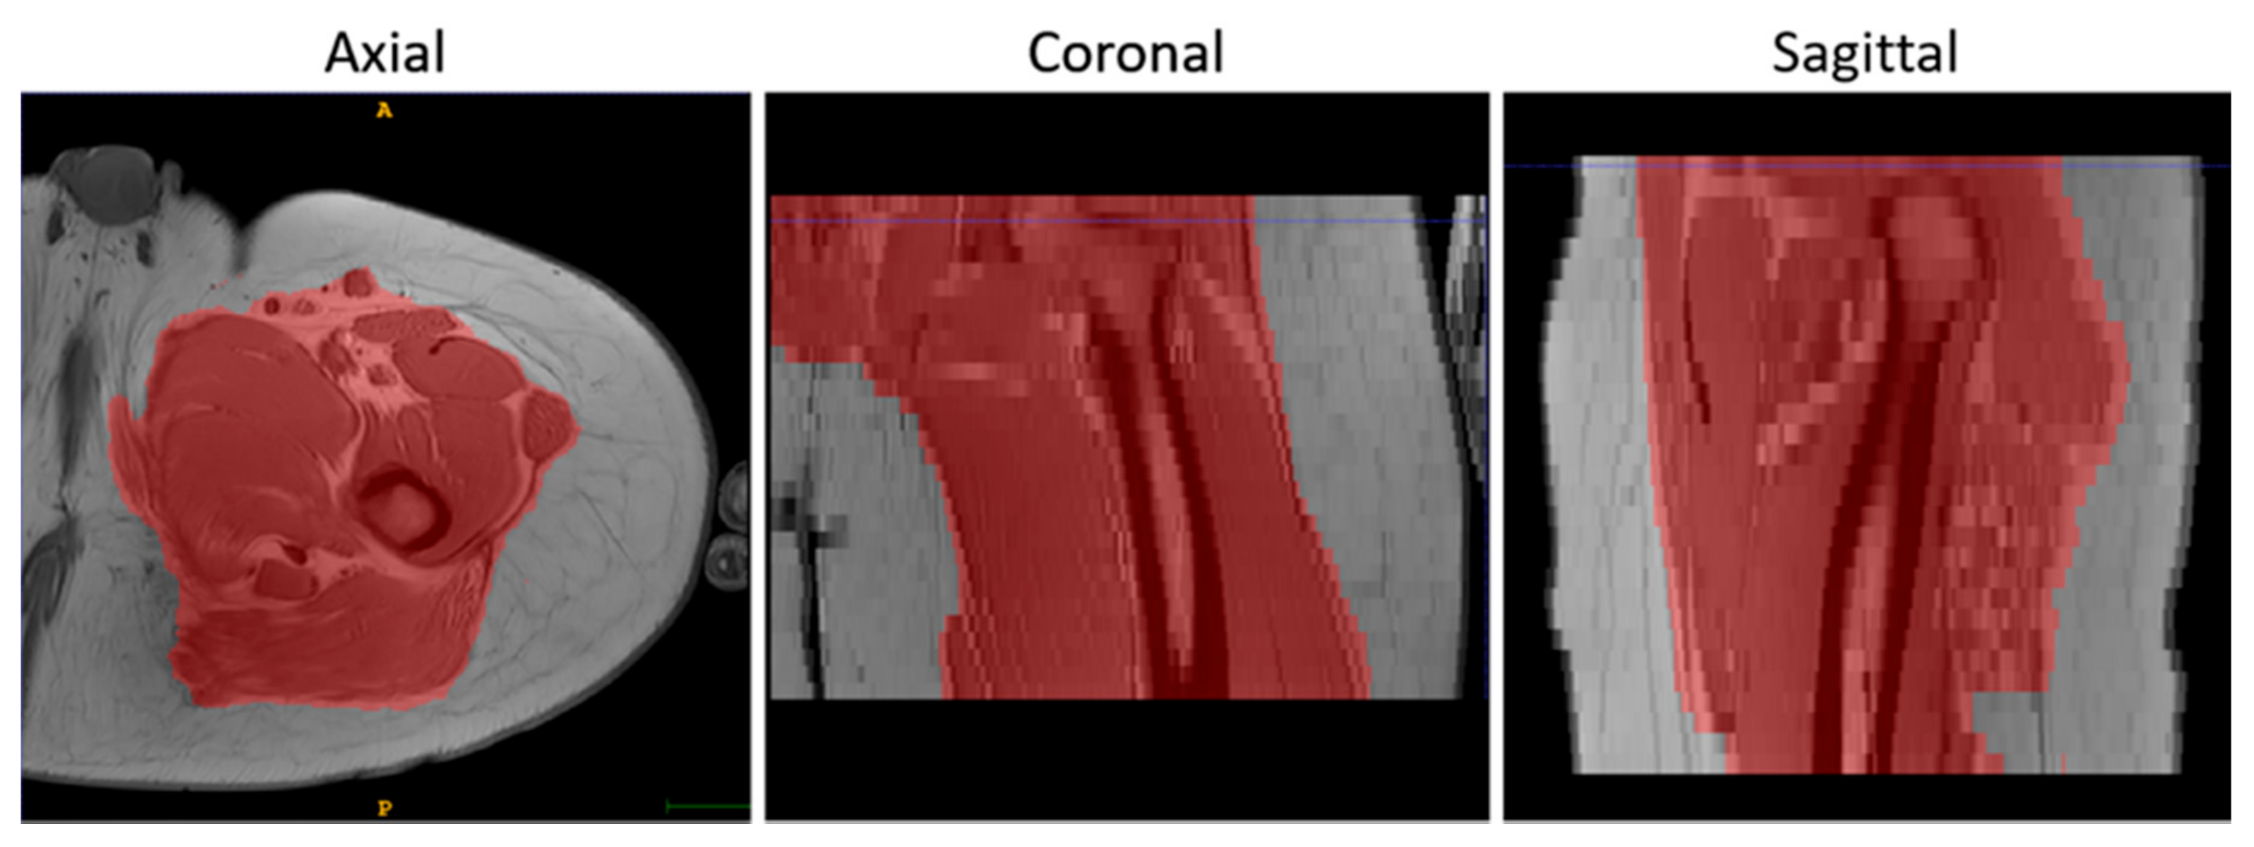

- To suppress the contribution of the subcutaneous fat, muscle volumes were selected using the semi-automatic segmentation tool of ITK-Snap (v3.8.0) [34] before registration and used as masks to calculate the similarity metric, as shown in Figure 2.

Figure 2. An example of the results of the masking step on T1-w MR images in 3 orthogonal views. - Finally, the voxels of the images were made isotropic to account for the sampling unevenness to improve the registration performance along the slice direction (final voxel resolution was 1×1×1 mm3).